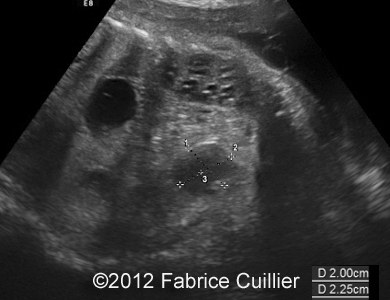

At 38 weeks, the dilatation has increased with significant meconium retention.

Image 10, 11: At 38 weeks, dilatation has increased with significant meconium retention.

8B

8D